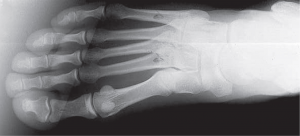

Τα περισσότερα κατάγματα εκ κοπώσεως συναντώνται στα κάτω άκρα. Η κνήμη είναι το οστό που προσβάλλεται συχνότερα και ακολουθούν η περόνη, τα οστά του ταρσού, τα μετατάρσια, το μηριαίο οστό και ο ηβικός κλάδος της λεκάνης. Πρακτικά μπορεί να συμβούν σε οποιοδήποτε οστό υπόκειται σε συνεχείς επαναλαμβανόμενες φορτίσεις.

Οι ακτινογραφίες συχνά είναι αρνητικές τις πρώτες εβδομάδες και μπορεί να χρειαστεί αξονική τομογραφία, σπινθηρογράφημα οστών ή μαγνητική τομογραφία για να τεθεί η διάγνωση.